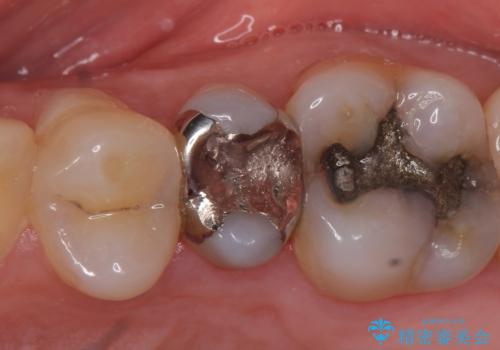

PGA(ゴールド)インレー しみる歯の治療